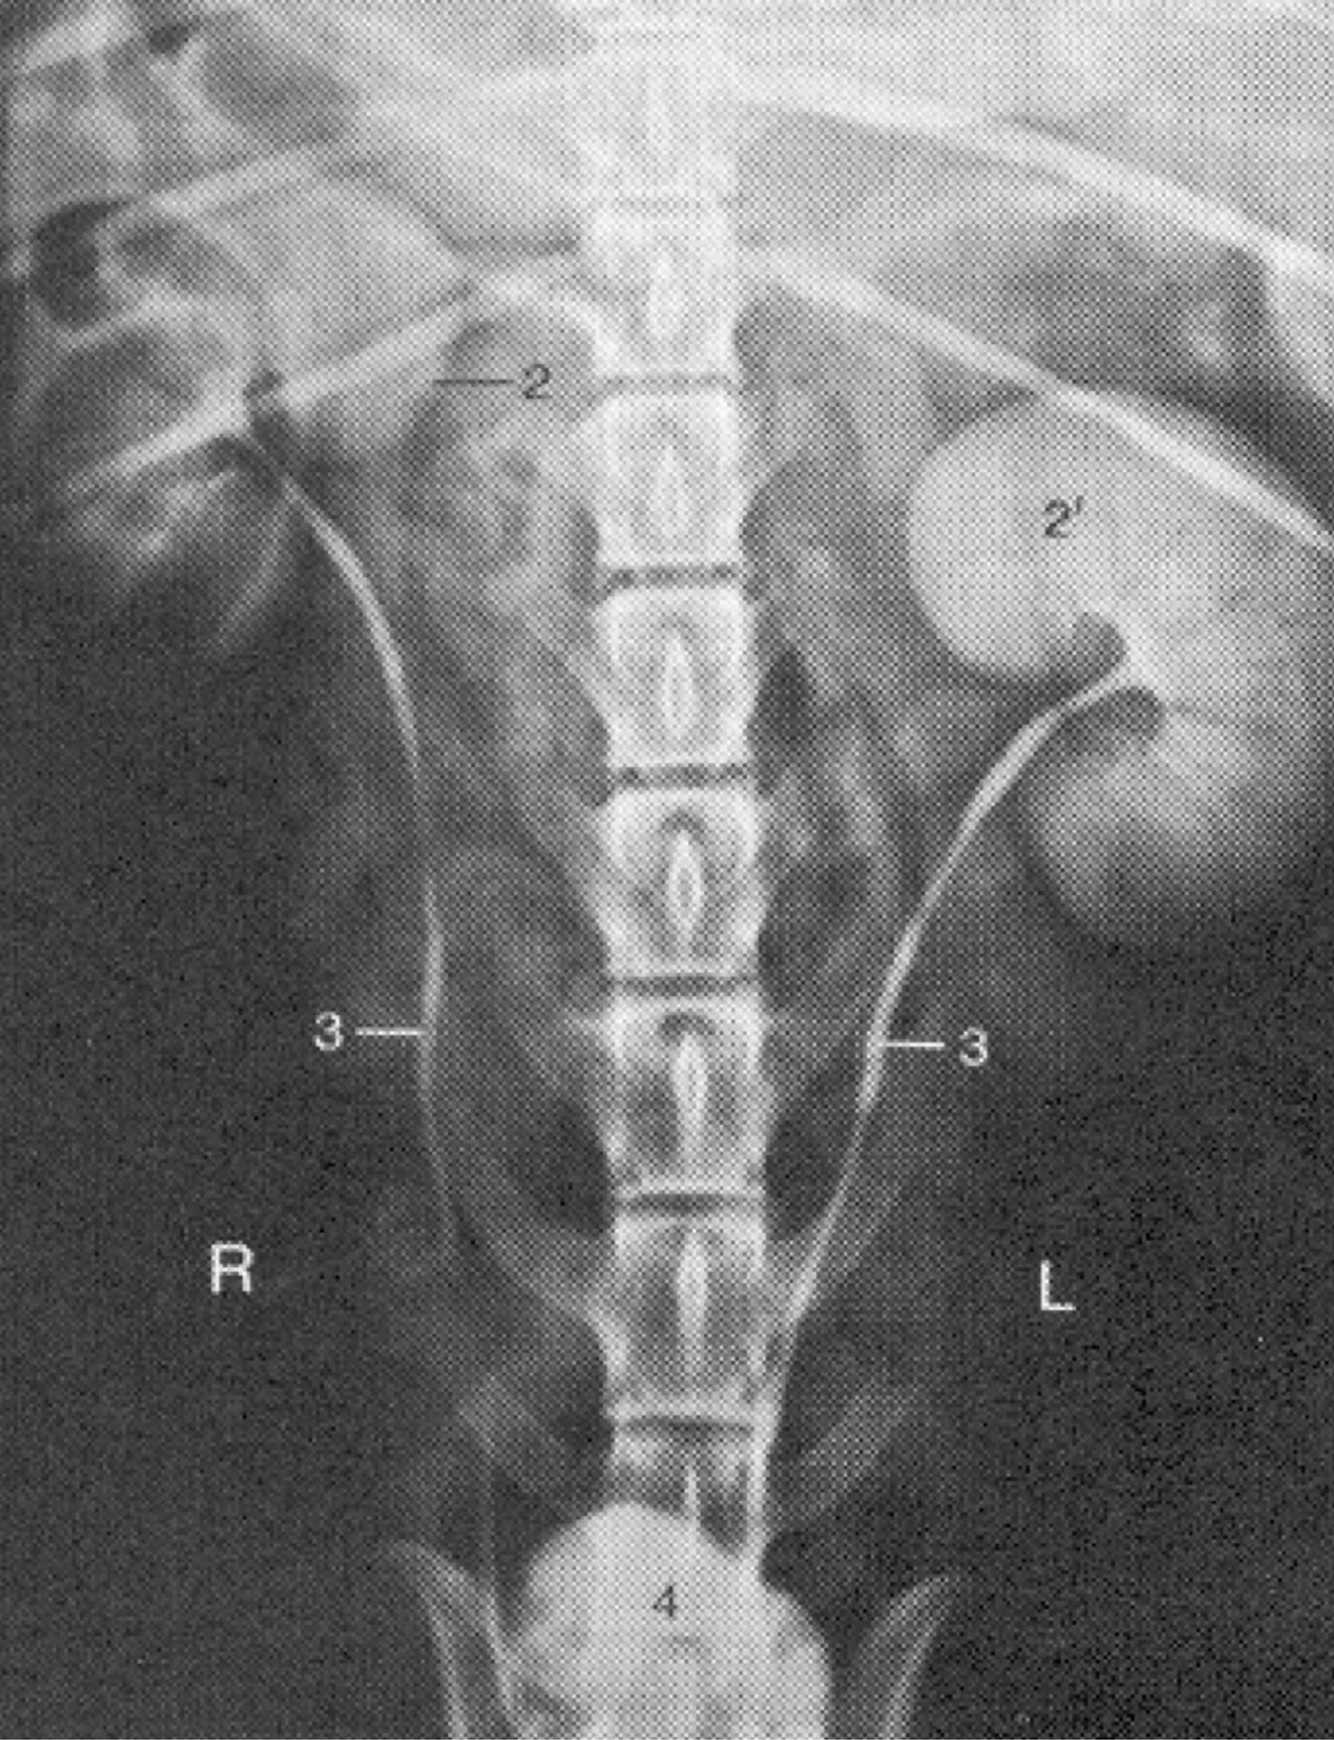

Label the diagram (2, 2’, 3, 4)

A

2, 2’: Kidneys

3: ureters

4) urinary bladder